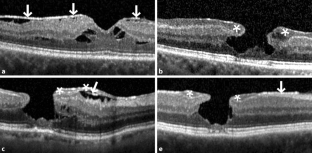

Abb. 2